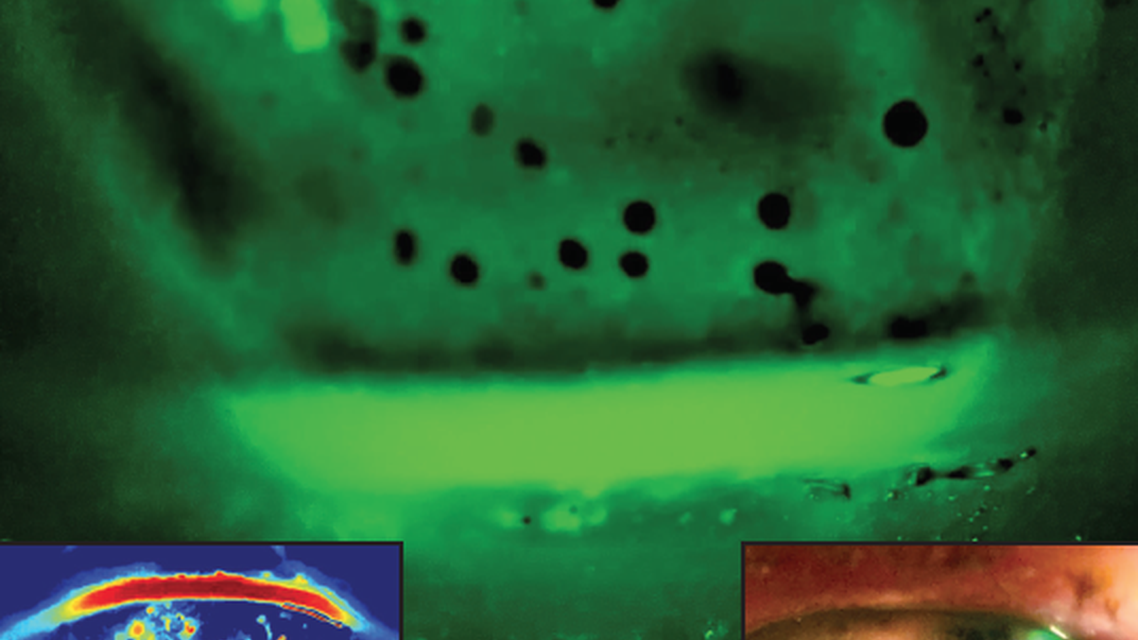

Bullous keratopathy is characterized by stromal edema and anterior corneal bullae (Figure) rooted in the loss of corneal endothelial cell integrity and function. Clinically, patients with this corneal pathology present with decreased vision and ocular pain caused by the epithelial manifestation of the disease, specifically the ruptured and intact epithelial bullae. As for the patient shown, endothelial damage was presumed to have been caused by the multiple surgeries she underwent to control her glaucoma, including a Baerveldt shunt (Johnson & Johnson Vision).